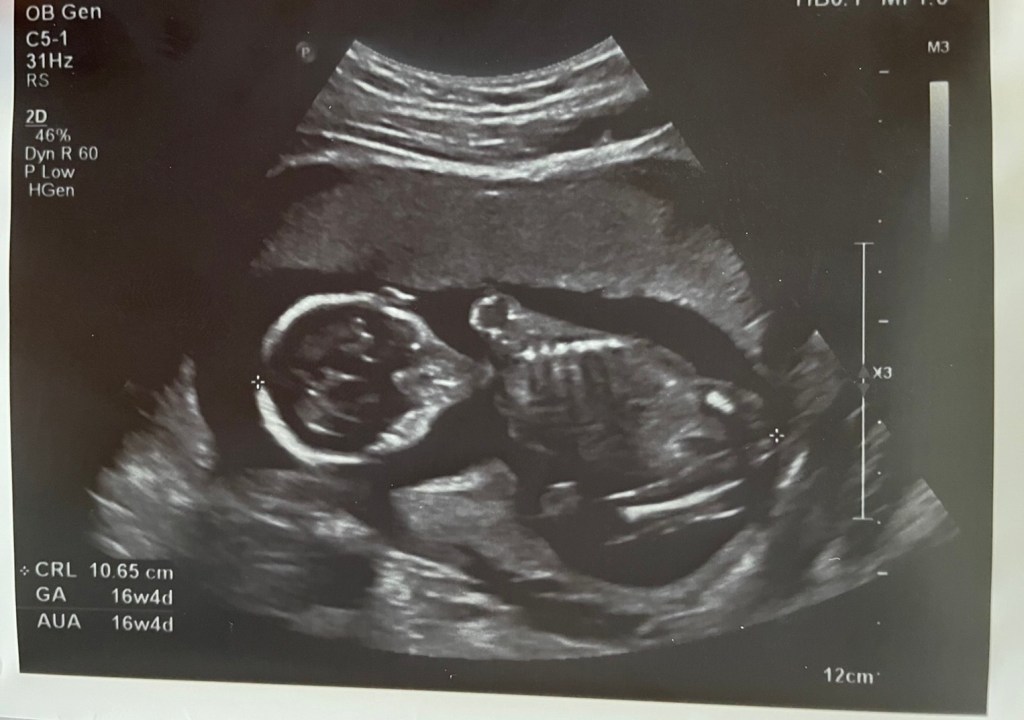

剛好有個朋友預產期跟我差不到一週,就想說那一起來揭曉性別好了,辦個簡單的性別派對,於是十六週產檢那天就請醫生幫我們把性別寫在紙條理,等性別派對再揭曉,看超音波的過程中,醫生看得很快,也沒有叫我們不要看,醫生就知道性別了,我就跟老公說應該是男的,不然不會看這麼快哈,老公的表情瞬間感覺到很失落,因為他也覺得很有可能,才發現原來還是有期待是女鵝比較多的XD

緊張的時刻到來,大家投完票後,兩位爸爸各自拿著對方醫生寫的小紙條,互相公開性別,我老公內心想要女兒,朋友老公則是想要兒子,結果老天捉弄人,結局完全相反,所以我的肚子裡的是男寶啦!家人都覺得很不可思議,因為我跟老公家裡各有三個妹妹跟三個姊姊,還以為生女寶的機率很高哩,大家還想說會不會醫生看太快沒看清楚,等高層次的時候要再確認一次,老公心裡可能也默默期待著還有翻盤的機會吧XD。